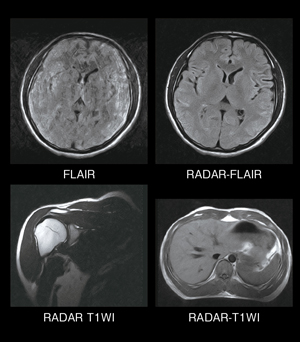

1.RADAR

“RADAR”(RADial Acquisition Regime)は日立独自の手法によるRadial Scan技術を用いたモーションアーチファクトの低減機能です。一般的に用いられているFSE法だけでなく,SE法やDWIにも応用できます。シーケンスの自由度が高く,撮像部位,撮像断面などによらず幅広く適用して,ルーチン撮像に効果を発揮します。さらに,撮像時間を大幅に高速化するパラレルイメージング技術(RAPID:Rapid Acquisition through a Parallel Imaging Design)を併用して,撮像時間を短縮することも可能としました。

モーションアーチファクト低減技術

超電導MRIシステムで評価の高いモーションアーチファクト低減技術“RADAR”を搭載しました。k空間のデータ取得を回転状に充填するRadial Scan技術により,位相エンコード方向のアーチファクトの特異的な収束を分散し,k空間中心のデータ取得タイミングを増加することで加算効果も期待できます。日立のRADARの特長は,ルーチン検査に使用できる汎用性と,SE法に適用して良好なT1コントラストが得られることです。

永久磁石MRIはモーションアーチファクトが目立ちにくい性質がありますが,さらにRADARの併用により,モーションアーチファクトの少ない良好な画像を得ることができます。図7にRADARの画像例を示します。頭部の画像は動きのある被検者に適用した例です。肩関節や腹部の呼吸動にも対応し,呼吸同期のない撮像でも良好な画像が得られます。

図7 RADAR画像例